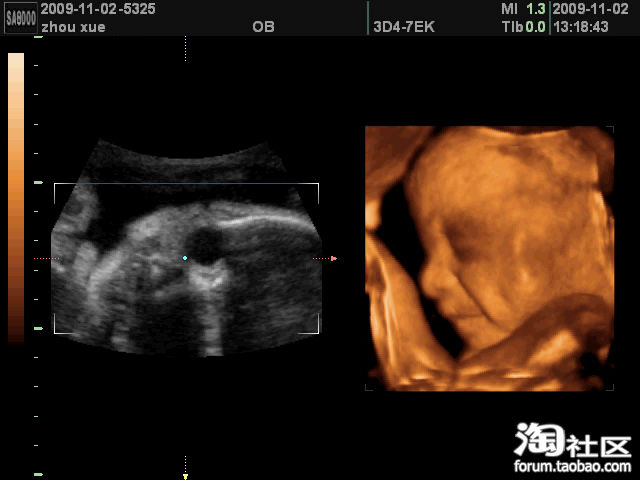

照得照片清楚,这不吗,连酒窝都照出来了。

这会他刚好是在笑,一笑,深深地一个酒窝露出来了,相当迷人呀

下午一点多,我们回到贝贝宫得再照,哈哈,成了

他先是用小手挡着嘴,不让我们看,高高的鼻子精巧的嘴型与我极像